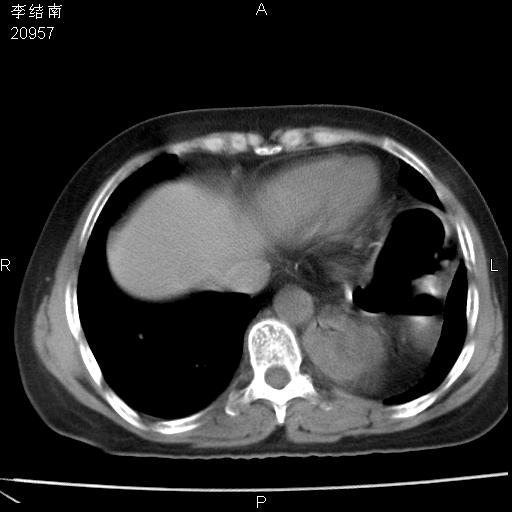

患者女,45岁,以右侧腰部包块来就诊,局部有压痛,皮肤颜色正常。因为是熟人扫的范围较大,患者有胆结石,胆源性胰腺炎病史。请大家看看,有手术病理。

可能大家觉得片子的质量不好,当时是做下腹部扫描,所以没有常规喝水,右腹壁的病灶当时是,密度不均有钙化影,局部骨质没见破坏,肝脏应该是受压的表现,所以当时考虑为腹壁的良性占位,各位老师考虑的神经源性肿瘤,我当时还真没想到,胰腺是胰腺炎治疗后改变.膈脚旁的混杂密度包快不好考虑什么,到上级医院做增强(腹部)+肺部平扫后,发现腹壁的病灶呈不均匀性强化局部可见囊性灶,当时考虑为腹壁结核,最具戏剧性的是膈脚旁的混杂密度灶确是胃的一部分,而腹壁的病灶确是脂肪瘤(简直不可思议)但是我亲眼所见在我们县医院开的.

很不好意思 ,患者后来手术切口裂开,临床医生作了病理证实是腹壁结核。

[病理诊断] CT13183腹壁结核!